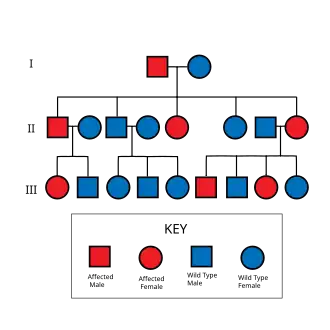

Neurofibromatosis type I (NF-1), or von Recklinghausen syndrome, is a complex multi-system neurocutaneous disorder caused by a subset of genetic mutations at the neurofibromin 1 (NF1) locus. Other conditions associated with mutation of the NF1 gene include Watson syndrome.[2] NF-1 is a gene on chromosome 17 that is responsible for production of a protein (neurofibromin) which is needed for normal function in many human cell types. NF-1 causes tumors along the nervous system that can grow anywhere on the body. NF-1 is one of the most common genetic disorders and is not limited to any person's race or sex. NF-1 is an autosomal dominant disorder, which means that mutation or deletion of one copy (or allele) of the NF-1 gene is sufficient for the development of NF-1, although presentation varies widely and is often different even between relatives affected by NF-1.[3]

The severity of NF-1 varies widely, and little is known about what causes a person to have more severe or less severe symptoms. Even within the same family (as there is a 50% chance that a parent will pass their condition to their offspring), levels of severity can vary enormously.[3] 60% of people with NF-1 have mild cases, with few symptoms that have very little effect in their day-to-day lives. About 20% of people with NF-1 have what are considered moderate cases, with several symptoms that usually have a few cosmetic effects. The other 20% have severe cases, with several symptoms that affect the person's quality of life. Even in this last group, symptoms are rarely life-threatening.[6]

Inheritance and spontaneous mutation

People with NF-1 have a 50% percent chance of passing the disorder to their offspring, but people can have a child born with NF-1 when they themselves do not have the condition. This is caused by a spontaneous mutation.